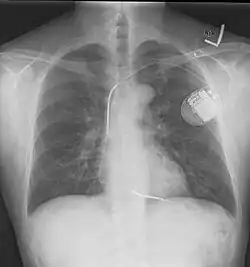

A chest radiograph, chest X-ray (CXR), or chest film is a projection radiograph of the chest used to diagnose conditions affecting the chest, its contents, and nearby structures. Chest radiographs are the most common film taken in medicine.

Chest radiographs are used to diagnose many conditions involving the chest wall, including its bones, and also structures contained within the thoracic cavity including the lungs, heart, and great vessels. Pneumonia and congestive heart failure are very commonly diagnosed by chest radiograph. Chest radiographs are also used to screen for job-related lung disease in industries such as mining where workers are exposed to dust.[3]